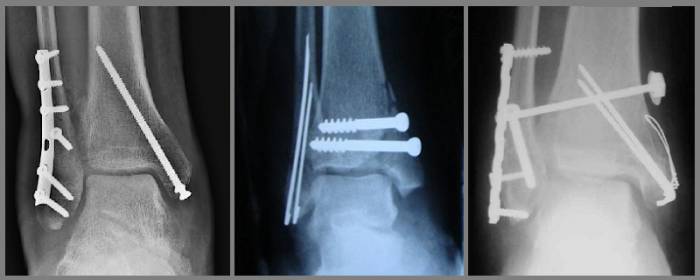

Остеометаллосинтез — основной метод хирургического лечения. Он выполняется с использованием спиц, стержней, пластин и винтов. При оскольчатом переломе часто применяется аппарат Илизарова, который сокращает время восстановления функциональности конечности.

Трехлодыжечные переломы лечатся хирургическим путем, включая физиотерапию. Большинство трехлодыжечных переломов лечат методом открытой репозиции с внутренней фиксацией (ORIF). Цель операции ORIF — выровнять сломанные кости для правильного срастания.